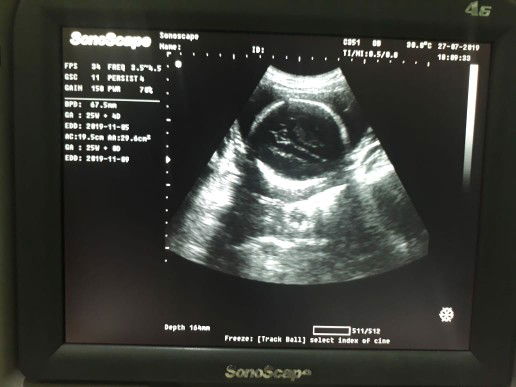

foto usg ank ku

Sehat truz ya ank cwek ku